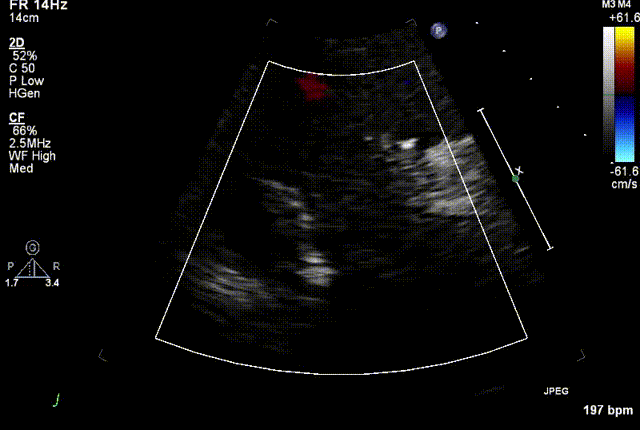

结合术前CT评估结果,葛均波院士团队最终决定选用LuX-Valve Plus 50mm和55mm两种型号的瓣膜,并于2021年11月30日顺利完成LuX-Valve Plus经血管三尖瓣置换术,手术室即刻拔除气管插管,术后第二天转出心内科监护室,下床活动。术后患者三尖瓣反流症状得到显著改善,复查心超结果显示人工三尖瓣瓣膜支架固定稳定,瓣叶关闭形态未见异常,未见明显反流。

复查心超图

在本次救治性临床研究中,治疗的两例患者病因不同解剖结构复杂,均为极重度三尖瓣反流,手术最终都顺利植入了LuX-Valve Plus三尖瓣人工瓣膜。术后超声显示瓣膜支架固定稳定,反流症状显著改善,取得了良好临床治疗效果。